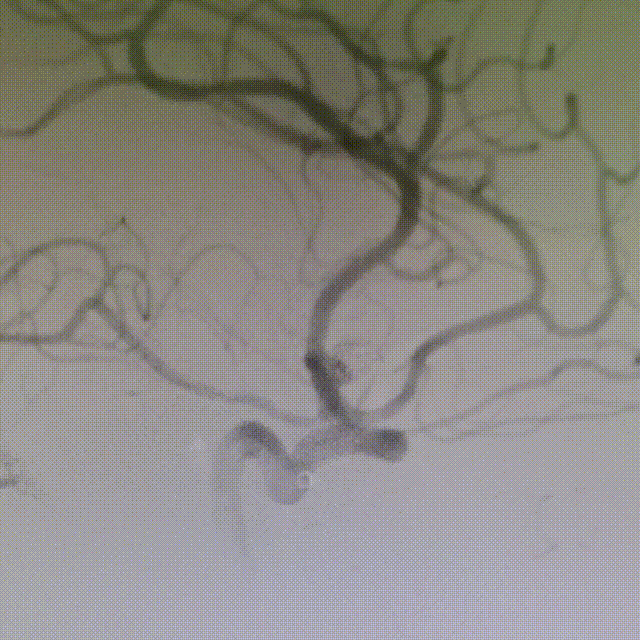

术后即刻工作位造影显示,支架全程打开形态良好,充分贴壁。

术后即刻正/侧位造影显示:各分支血管血流通畅,无出血情况,瘤体内无造影剂充盈。

术后3D造影:支架打开充分,全程贴壁,各分支血管血流通畅,可看到内翻的Mark点也被Evolve贴到了血管壁上,充分体现了Evolve足够强的径向力,预示着Evolve对动脉瘤合并狭窄应用或许是一个不错的选择。